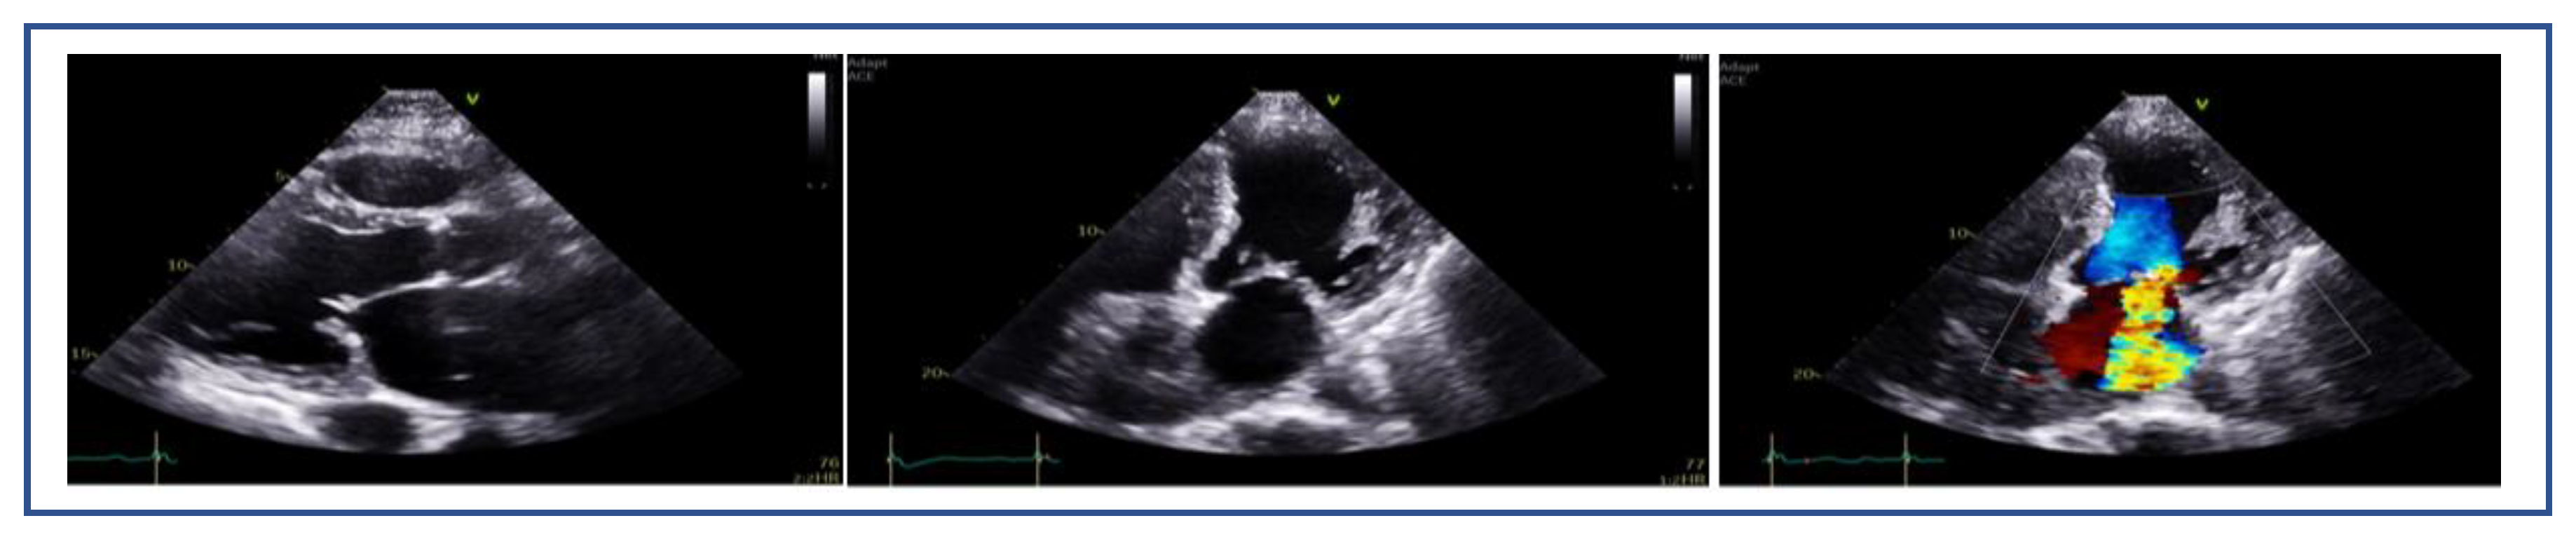

7.3. Mitral Valve Area and Gradient

7.4. Flail Gap and Width (PMR)

7.5. Tenting Height and Coaptation Length (SMR)